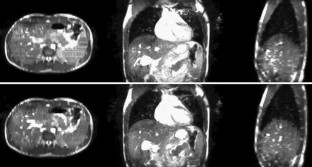

Fig. 1

Fig. 2

Fig. 3

Fig. 4

Fig. 5

Fig. 6

Fig. 7